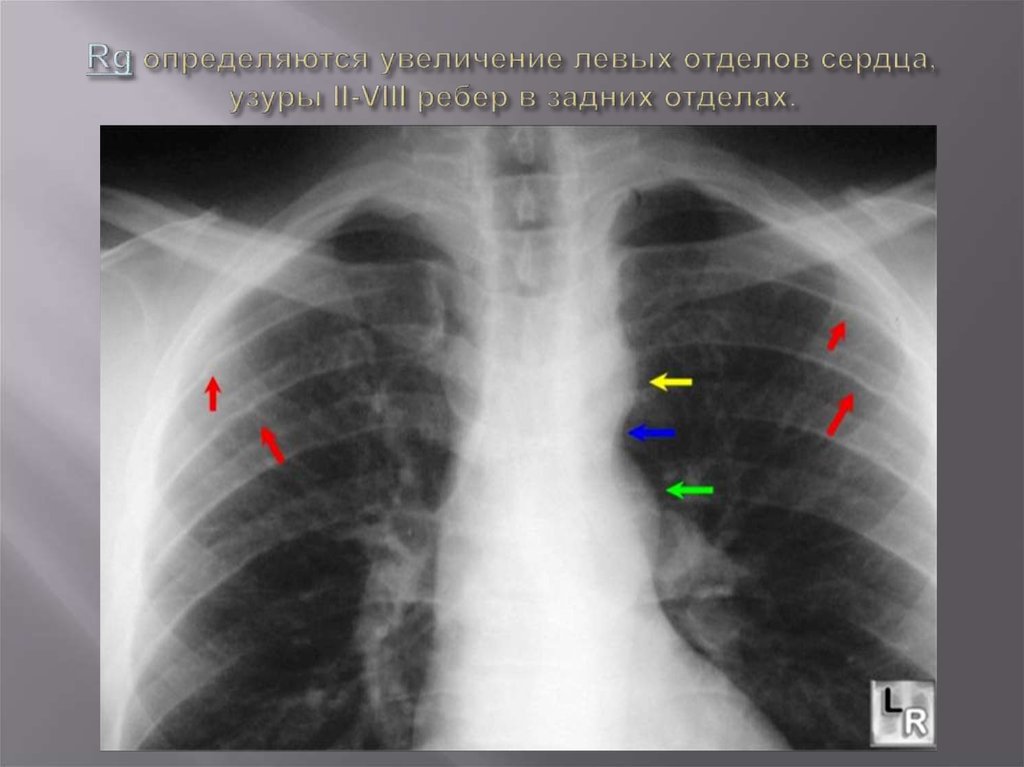

Rg определяются увеличение левых отделов сердца, узуры II-VIII ребер в задних отделах.

5. Rg определяются увеличение левых отделов сердца, узуры II-VIII ребер в задних отделах.